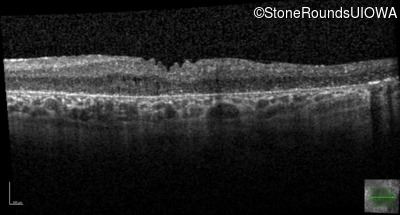

Optical Coherence Tomography - Right - 20/150

Exemplar / OCT Stack

OCT Stack